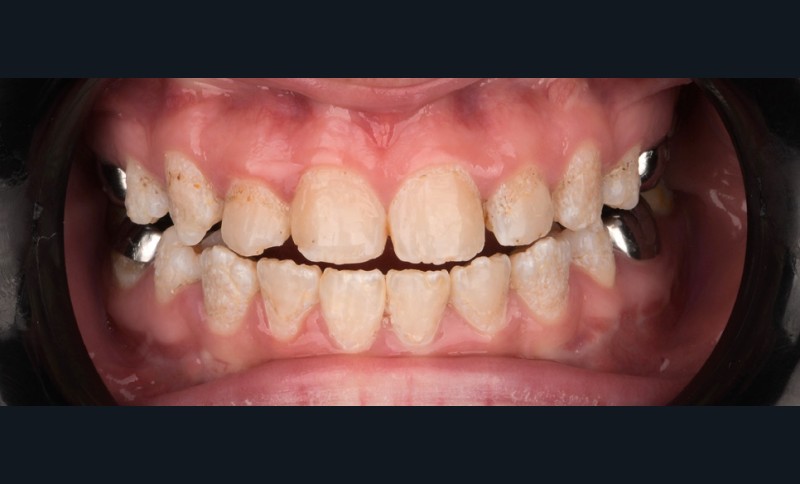

Lors de l’arrivée de la patiente, un examen clinique au fauteuil est effectué, complété par une empreinte numérique permettant l’enregistrement précis des arcades dentaires et de l’occlusion existante. Cet examen initial met en évidence une pathologie de type amélogenèse imparfaite. On note également la présence de couronnes métalliques au niveau des premières molaires, ainsi que de multiples restaurations, notamment au niveau des dernières molaires (fig. 1 à 4).